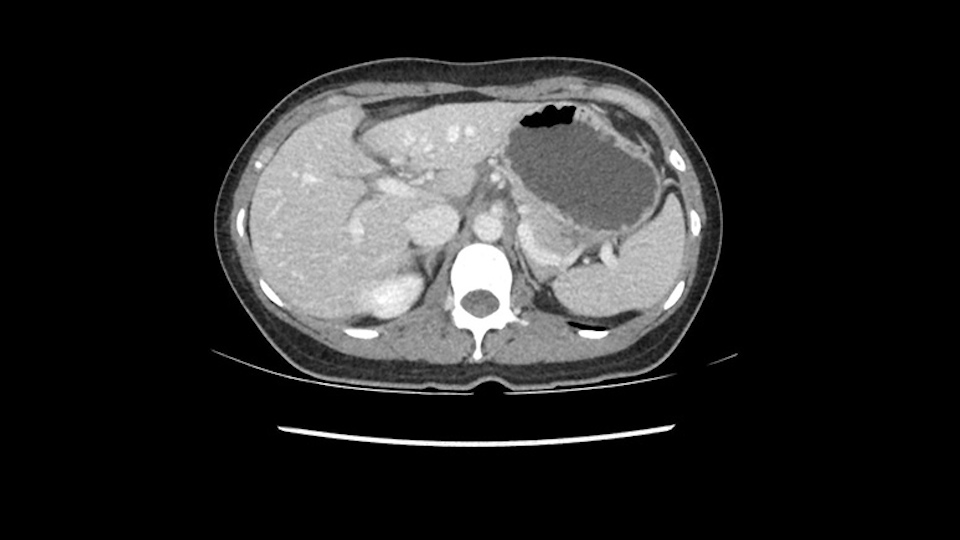

When you see the axial sections of the scan, you find it's a largely exophytic mass and its well-encapsulated. So this is typically true of a well-differentiated hepatocellular carcinoma. If you look at this, this is the gallbladder which is being displaced to the right and the mass is in the Sg4 of the liver, exophytic, projecting down. As it is coming down, it is also displacing the duodenum and the head of the pancreas which is being pushed towards the left and it's going right up to the cava, the start of the anterior surface of the cava. Obviously getting a lot of collaterals and vascularity from all the vessels around but one has to be very careful in evaluation of the main portal pedicle in this particular case and of course arterial inflow to the Sg4 and of course the left lobe of the liver.

Now let’s look at some specific anatomical points for planning this surgery. First thing you see when you see a left hemihepatectomy is that where is the left portal vein and the right portal vein branching? And what is the stump of the left portal vein available for you for ligation? In this particular case, you’ll find that there’s overhanging of the tumor but left portal vein pedicle is sufficiently available for us for ligation.

Now coming to the duodenum, we can see that the stomach is coming down, and as it comes down to the head of the pancreas, it’s compressed by the mass which is distorting the duodenum completely. Is there invasion of the duodenum or not? When you see a little above, there is a very well nicely capsulated tumor so my impression is that it is only displacing the duodenum, may not be invading the duodenum. But however intraoperatively one has to be careful in dissecting the duodenum from the tumor.

The cava however is again displaced by this well encapsulated mass, so I would expect that I should be able to lift out of the cava with some moment of careful dissection and the cava is not infiltrated by this tumor. Most of the tumor is below the portal plane and the hepatic-venous vein is completely free. You have the left and the middle hepatic vein joining together and opening up. The right hepatic vein is as usual. All the superior segments of the liver are intact so we do not expect any major problem in this particular case as far as the venous outflow is concerned. So this is about the preoperative planning as far as this case is concerned.

So in planning for this operation, as I look at the scans, I first visualize the arterial phase and I can see that there’s are a lot of big feeding arteries to this large tumor. Likely all the right side vessels feeding the right side of the liver: right hepatic artery and likely the Segment 4 artery are spared from the tumor. It’s likely the left hepatic artery is ramificating and giving feeding arteries to this tumor. It certainly looks like a large mass that its compressing other structures like the cava, the pancreas, the stomach; but I think there’s a plane and we can see that better in the venous phase. There’s a plane of separation between the gallbladder, the pancreas, the cava, that this tumor is abrupting but likely not invading. Usually, these masses actually don’t invade at that level and basically are pushing the tissues and once you open, you’re able to separate the tumor. Sometimes there’s some adhesions but you can actually separate and there’s usually no invasion.

Lo siguiente que voy a hacer es mirar a la fase venosa. Y otra vez parece que todas las estructuras yendo al hígado derecho, es decir, tanto la vena porta derecha, la vena porta principal parece que están libres de tumor. Lo que si parce es que este tumor está comprimiendo diferentes estructuras, parece que comprime el páncreas, puede que este comprimiendo la cava, la vesícula biliar, pero en la mayoría de estos casos estos tumores no invaden estas estructuras, muy probablemente sea simplemente compresión, y una vez hallamos hecho la laparotomía es probable que todas estas estructuras queden separadas del tumor y puede que haya algunas adherencias que se puedan resecar sin problemas.